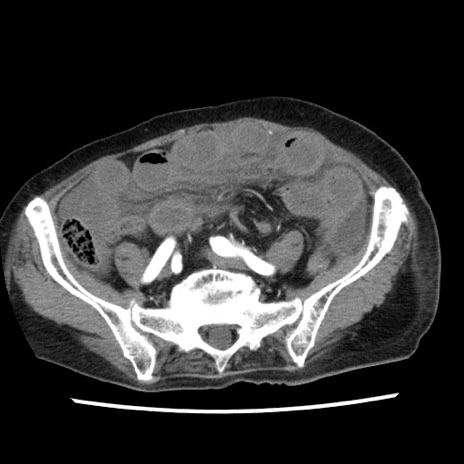

症例1(横断像)

【症例】80歳代女性

【主訴】腹痛

【現病歴】8時間前から腹痛あり来院。

【既往歴】糖尿病、脂質異常症、子宮体癌にて子宮全摘術

【身体所見】意識清明・会話良好だが腹痛で苦悶様、全腹部にわたって反跳痛と圧痛あり

【データ】WBC 13600、CRP 0.14、LDH 224、CK 90